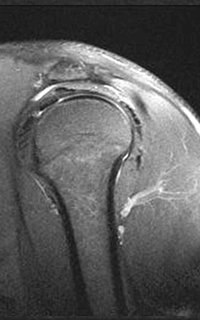

As some say, seeing is believing. Check out the images below which compares a low strength, open machine to a 1.5T, high-field machine. The difference in quality from one scan to another speaks for itself.

MRI of the Shoulder: High-field 1.5T MRI on the left; low-field, open on the right.